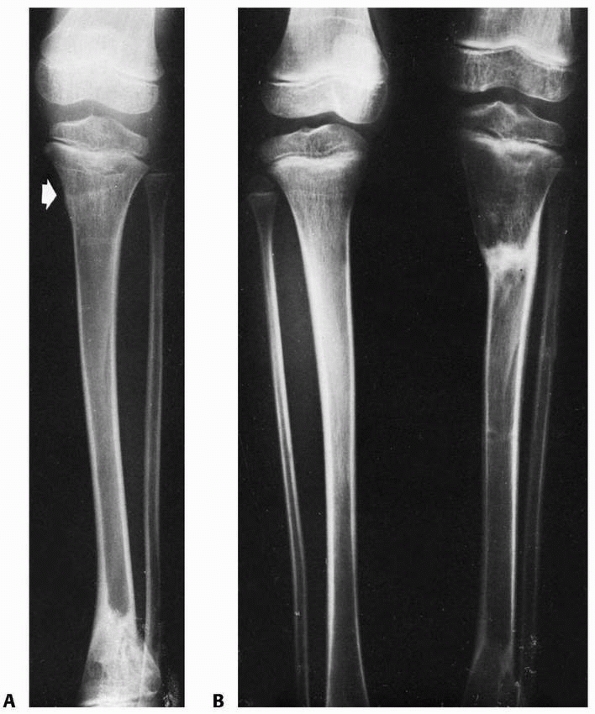

![]() |

|

FIGURE 25-8 Developmental valgus after a proximal tibial metaphyseal fracture and subsequent corrective osteotomy. A.

Radiograph taken 6 months after a fracture of the proximal tibia. The injury was nondisplaced. The scar from the initial proximal metaphyseal fracture is still seen (arrow). This child developed a moderate valgus deformity of the tibia within 6 months of fracture. B. A proximal tibial corrective osteotomy was performed. C. Two months postoperatively, the osteotomy was healed and the deformity corrected. D. Five months later, there was a recurrent valgus deformity of 13 degrees. (Courtesy of John J.J. Gugenheim, MD.) |

FIGURE 25-8 (continues)